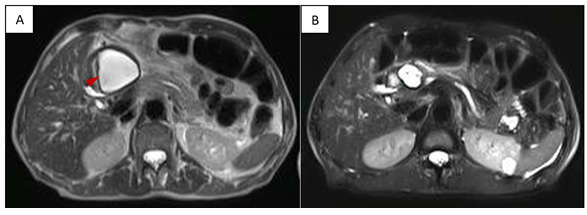

A 72-year-old female patient with a history of acute biliary pancreatitis, arterial hypertension, type 2 diabetes mellitus, and cholecystectomy. She presents 10 years after pancreatitis with 1 year of abdominal pain. Physical examination: evident protrusion and painful palpation in the left upper abdominal quadrant. Normal laboratory results. Contrast-enhanced CT and MRI showed an 11 x 9 cm pseudocyst. It was punctured with a 19G needle and two 9 cm x 7F double Pigtail stents were placed (Figures 3 & 4). After 6 months of follow-up, only residual inflammation was evident and the stents were subsequently removed. Favorable clinical outcomes (Figures 5 & 6).

Figure 3 Pre-drainage MRCP (T2 weighted image): Pseudocyst of the body and tail of pancreas (asterisk) that exerts compressive effect on stomach, small bowel and left kidney.